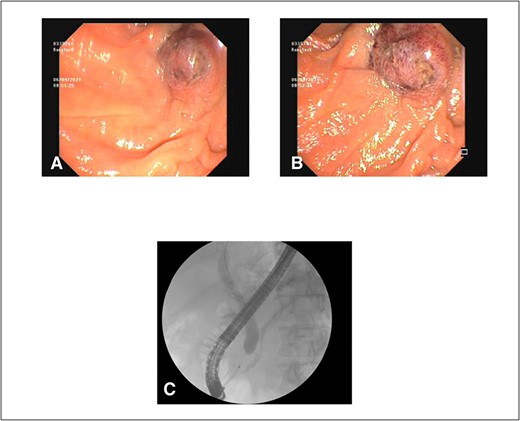

After consultation with our Hepatobiliary service, the consensus was for the patient to undergo an urgent ERCP. Intraoperatively, a duodenoscope was introduced through the mouth and was advanced to the duodenum at the ampulla of Vater. The major papillae were bulging and a malignant appearing infiltrative mass was visualized. A tapered tip cannula was inserted through the ampulla and contrast was injected, revealing a patent PD and a single 18-mm long stenosis of the distal third of the CBD with significant dilatation of the proximal CBD and intrahepatic ducts (Fig. 2). A 10Fr 7-cm transpapillary plastic stent was inserted with a single internal flap, 5.5 cm, into the CBD. The biliary pancreatic junction was biopsied with cold forceps for histology. Cholangiopancreatography revealed the stent was in good position with good flow of contrast into the duodenum beyond the filling defect (Fig. 3).

(A) and (B) endoscopic images showing a single plastic stent inserted into the distal CBD, protruding into the second part of the duodenum; (C) position confirmed on cholangiopancreatography revealing resolution of distal CBD filling defect.